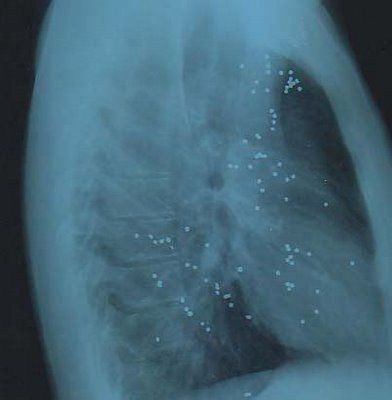

La presencia de polvo de sílice en el aire, que es respirado por las personas, conlleva la pérdida de elasticidad y permeabilidad de la pared alveolar de los pulmones, obstruyendo el normal intercambio de oxígeno y salida de dióxido de carbono.

El sílice que entra en los pulmones no sale de ellos y se mueve de célula en célula destruyendo todo a su camino. Las alteraciones que se presentan debido al sílice son irreversibles provocando la silicosis, una enfermedad progresiva y degenerativa. No existe tratamiento específico para la misma, quien la contrae no tiene la posibilidad de sanar, sólo se puede detener su avance. La silicosis tiene un largo período de incubación (vale decir que el afectado no tiene conocimiento de su enfermedad) y puede entre diez y veinte años en desarrollarse.

El óxido de silicio (IV) o dióxido de silicio (SiO2) es un compuesto de silicio y oxígeno, llamado comunmente sílice. Es uno de los componentes del arena. Una de las formas en que aparece naturalmente es el cuarzo. Consultando varias páginas dedicadas a la salud y a algunos médicos amigos, nos dicen que en su etapa inicial se presenta tos y secreción permanente, daños en los pulmones, falta de aire, coloración violácea de la piel, labios y mucosas. Luego se complica con problemas cardíacos, se acentúa la dificultad respiratoria, tos persistente con taquicardia. En su etapa final, el tórax aparece aplastado, hay insuficiencia cardiaca y pérdida total de la capacidad de trabajo.